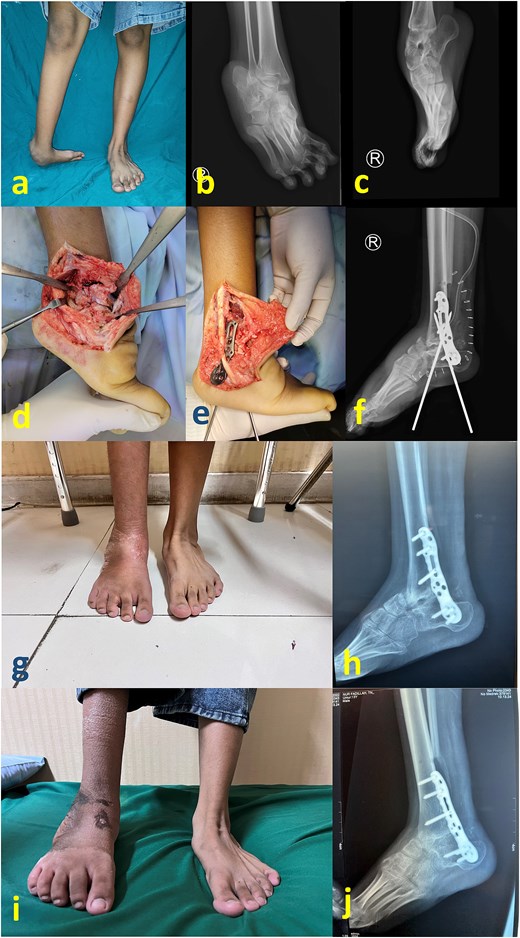

A generally healthy 26-year-old man presented to our clinic complaining of a long-standing deformity of his foot and ankle (Fig. 1a–c). The patient reported that treatment of childhood clubfoot was not acknowledged within his family construct. At the presentation, his main complaint was poor cosmetic appearance, although pain and gait difficulty were present. We decided to undergo single-stage correction with partial talectomy followed by tibiotalocalcaneal arthrodesis using a lateral plate (Agofix, Agomed Medizin-Technik GmbH, Germany). The distal tibia articular surface preparation was done using lateral transfibular approach prior to plate placement.

(a) Preoperative clinical images; (b) and (c) preoperative radiograph; (d) intraoperative image after partial talectomy followed by fixation with plate and screw; (e) immediate postoperative image depicting additional fixation with Schanz screw and external fixator; (f) immediate postoperative radiograph; (g) latest clinical images after 1 year postoperative; (h) and (i) latest radiograph after 1 year postoperative.

The patient was placed in the lateral decubitus position under regional anesthesia. The distal fibula was removed via the lateral transfibular approach. The plantar flexor tendon including the Achilles tendon was initially lengthened, but residual equinus remained due to bony obstruction as well as massive soft tissue contracture. Subsequent axial partial talectomy at the talar dome was performed as much as necessary to facilitate reduction. A lateral tibiotalocalcaneal plate that was applied to firm the ankle (Fig. 1d) was reinforced by a uniplanar external fixator (Fig. 1e and f). First metatarsal dorsal closing wedge osteotomy was completed to address the cavus midfoot. The surgical wound was irrigated and closed in a standard fashion.

An external fixator was worn for 1 month postoperatively and no weight bearing was permitted. Partial weight bearing was permitted 1 month following external fixator removal. The patient was allowed to begin full weight-bearing 2 months postoperatively while undergoing rehabilitation therapy, including proprioceptive exercise. Latest follow-up at 1-year postoperative period showed a stable and plantigrade ankle, with radiological signs of healed arthrodesis (Fig. 1g–i).

A 19-year-old woman presented with a crooked ankle and foot resulting from an untreated childhood clubfoot (Fig. 2a–c). The cause of this neglect was delayed diagnosis and treatment, as there was limited access to adequate healthcare facilities in her remote hometown.

(a) Preoperative clinical images; (b) and (c) preoperative radiograph; (d) intraoperative image after partial talectomy followed by (e) fixation with plate and screw; (f) immediate postoperative image depicting additional fixation with Schanz screw; (g) clinical images at 2 months postoperative (h) 2 months postoperative radiograph; (i) latest clinical images after 1 year postoperative; (j) latest radiograph after 1 year postoperative showing healed arthrodesis.

Similar to the first case, surgery via the transfibular approach, posteromedial tissue release, reduction facilitated by partial talectomy and tibiotalocalcaneal plate fixation were performed (Fig. 2d and e). For this patient, the fixation was reinforced with two Schanz screws that were inserted from the calcaneal plantar side (Fig. 2f). Compared with the first case, this patient’s leg was thinner with less deforming forces such that an external fixator was deemed unnecessary. Another reason for not removing these Schanz screws was to prevent the patient from prematurely bearing weight on the affected foot, as postoperative follow-up monitoring would be technically hindered. At 2 months postoperation, the Schanz screws were removed. The patient was allowed to gradually bear weight, transitioning from partial to full weight-bearing (Fig. 2g and h). Full healed arthrodesis with stable plantigrade ankle was achieved at 1 year postoperative follow-up (Fig. 2i and j).